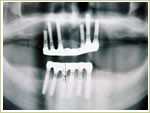

79歳 男性 インプラント埋入数:12本 画像拡大

治療中

治療中治療後